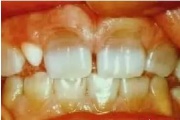

Fluoroos

Fluoroosi

Hammaste defektid